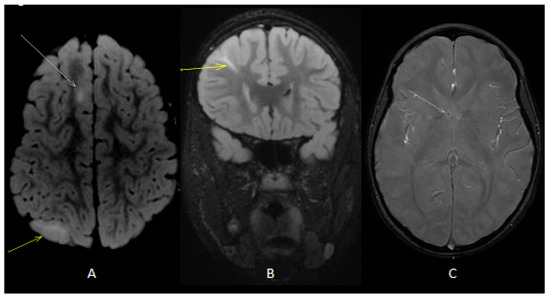

Figure 1.

Axial (A) T2 fluid-attenuated inversion recovery (FLAIR) image showed cortical (white arrow) and subcortical (yellow arrow) tubers. Coronal (B) T2 FLAIRimage showed radial band (yellow arrow). Axial T2 gradient echo (GE) image (C) showed subependymal calcific nodules along lateral ventricles (white arrow).